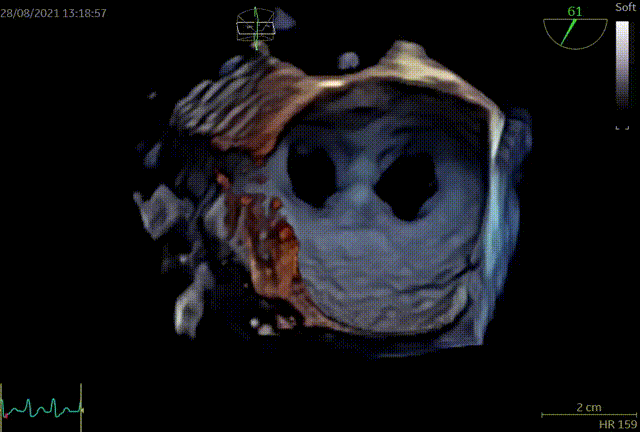

术前超声评估:

术前TEE提示重度功能性二尖瓣返流,返流位于A2/P2;

术前TEE提示二尖瓣重度返流,返流位置位于A2/P2区